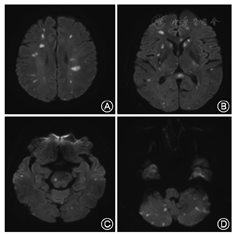

所有患者均有突然出现的肢体乏力、麻木、构音障碍等局灶性神经功能缺失的表现,在症状出现后的3 d内经头颅CT排除脑出血、头颅MRI平扫及DWI证实颅内有可以解释症状的新发病灶,且多数患者(36例,64.29%)头颅MRI显示出现分布于双侧大脑半球、小脑、脑干的多发脑梗死病灶(图1);21 d后再次行头颅MRI平扫和DWI证实上述病灶符合脑梗死改变,且无出血转化和癌性增生的征象;脑梗死发病后30 d,30例(53.57%)患者预后不良,其中死亡8例(14.29%)。